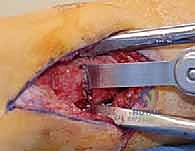

3. الشق الجراحي والوصول للعظم

يقوم الجراح بعمل شق دقيق (بأقل تدخل جراحي ممكن) في الجزء السفلي من الساق للوصول إلى عظمة الساق (Tibia) وأحياناً عظمة الشظية (Fibula) إذا تطلب الأمر.

4. قطع العظم (The Osteotomy)

هناك تقنيتان رئيسيتان يختار الدكتور هطيف بينهما بناءً على حالة المريض:

* تقنية الوتد المفتوح (Opening Wedge): يتم عمل شق في العظم وفتحه لإضافة طعم عظمي (صناعي أو من حوض المريض) لتعديل الزاوية.

* تقنية الوتد المغلق (Closing Wedge): يتم إزالة مثلث صغير من العظم، ثم إغلاق الفراغ لتعديل المحور.